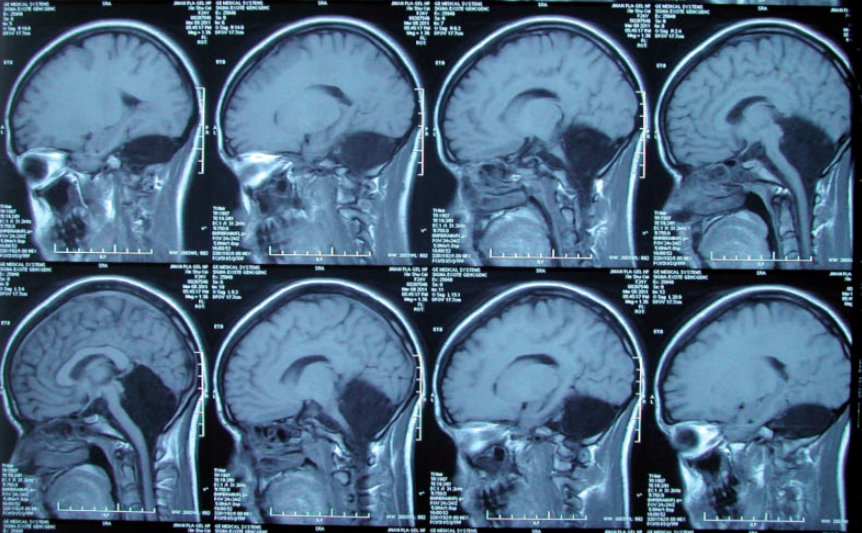

Проведя рутинную томографию мозга, врачи ужаснулись, увидев,

что пациентка полностью лишена мозжечка — важнейшей части мозга, расположенной в задней части черепа. Область, в которой должен находиться мозжечок, оказалась просто заполненной спинномозговой жидкостью.

«Компьютерная томография и магнитно-резонансная томография не показали никаких следов тканей мозжечка, доказав его полное отсутствие», — резюмировали ученые в статье в журнале Brain, в которой они описали уникальный случай.